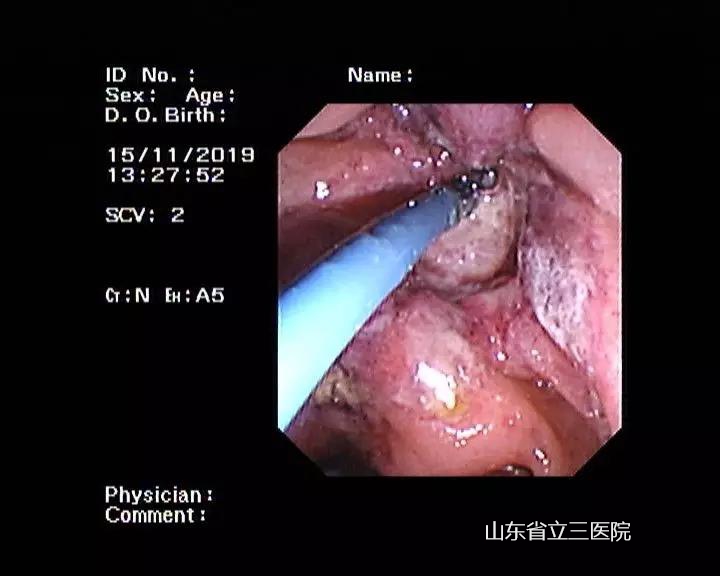

患者光動(dòng)力治療一個(gè)月后發(fā)現(xiàn)腫瘤已壞死脫落

省立三院肝膽外科結(jié)合患者體征特點(diǎn),與患者家屬充分溝通后,在11月14日、15日先后為患者進(jìn)行了兩次內(nèi)鏡下光動(dòng)力手術(shù)治療。手術(shù)過(guò)程中,張锎主任與團(tuán)隊(duì)密切配合,運(yùn)用嫻熟的ERCP技術(shù)將半導(dǎo)體激光插入患者膽總管下段及十二指腸乳頭處,對(duì)腫瘤進(jìn)行照射,并在膽總管內(nèi)放置了塑料支架,保證患者膽汁流出通暢。兩次手術(shù)過(guò)程均迅捷順利,患者術(shù)后快速恢復(fù),2020年1月8日來(lái)院復(fù)查時(shí),發(fā)現(xiàn)十二指腸乳頭腫瘤已經(jīng)壞死脫落,手術(shù)完全達(dá)到了預(yù)期效果。